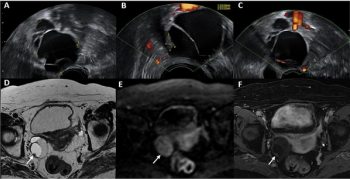

New research shows that pelvic MRI offers equivalent sensitivity but nearly 20 percent greater specificity than transvaginal ultrasound for the classification of adnexal lesions.